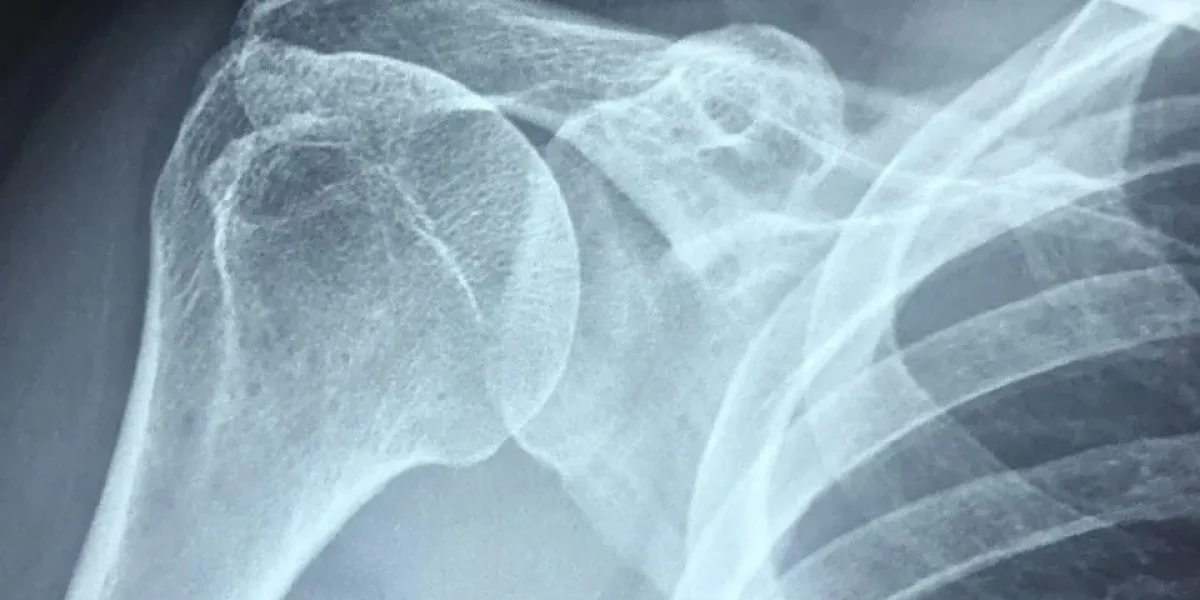

x-ray style image of human shoulder